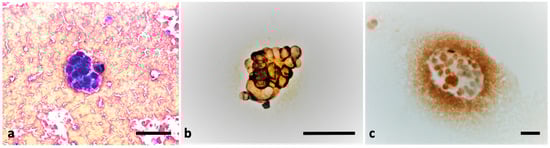

2. Case Presentation